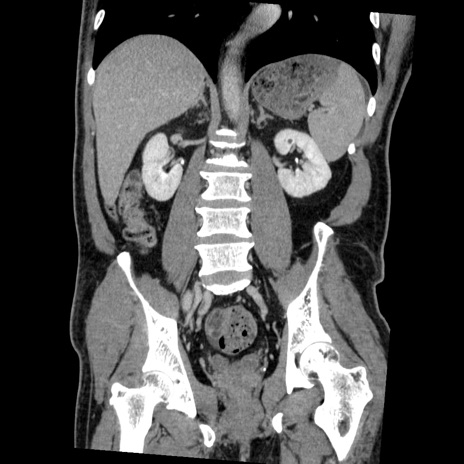

症例22(冠状断像)

【症例】50歳代男性

【主訴】腹痛

【現病歴】AVMからの被殻出血のため回復期リハ病棟入院中。 本日午後3時頃急に下腹部痛が出現した。

【既往歴】AVM、被殻出血、虫垂炎、高血圧

【身体所見】意識晴明、左半身不全麻痺、会話の理解は良好、36.5°C、腹部:膨隆、全体に板状硬、下腹部正中に圧痛点あり、反跳痛-、筋性防御不明、右下腹部にope scar

【データ】WBC 9400、CRP 0.06